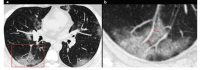

A new type of coronavirus (2019-nCoV) is rapidly spreading worldwide and causes pneumonia, respiratory distress, thromboembolic events, and death. Chest computed tomography (CT) plays an essential role in the diagnosis of viral pneumonia, monitoring disease progression, determination of disease severity, and evaluating therapeutic efficacy. Chest CT can show important clues of 2019-nCoV disease (also known as COVID-19) in patients with an appropriate clinic. Prompt diagnosis of COVID-19 is essential to prevent disease transmission and provides close clinical observation of patients with clinically severe disease. Therefore, radiologists and clinicians should be familiar with the CT imaging findings of COVID-19 pneumonia. Herein, we aimed to review the imaging findings of COVID-19 pneumonia and examine the critical points to be considered for imaging in cases with COVID-19 suspicion.